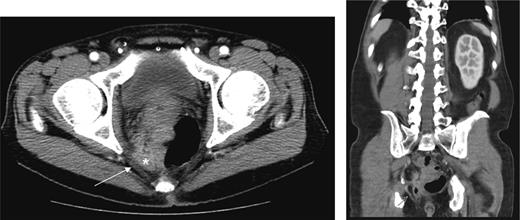

In the 6-week follow-up, repeat CT demonstrated eccentric thickening of the rectosigmoid with interval development of an adjacent complex pelvic fluid collection with supralevator extension measuring 3.5 × 2.5 cm (Fig. 2a and b). Percutaneous needle biopsy revealed pus, and a drainage catheter was left in place (Fig. 3a and b). The patient did not improve, was reimaged and was found to have collection extending into the ischiorectal fossa and supralevator space (Fig. 4). Owing to refractory pain and persistent leukocytosis, the patient was taken to the operating room for examination under anesthesia. No fistulous tract or internal drainage was noted within the rectal vault; however, consistent with the imaging, external induration was observed along the right ischiorectal fossa, where, upon incision, a large purulent cavity was evacuated. On evening rounds, the patient was noted to have a marked leukocytosis and frank stool coming from the ischial wound, and he was taken emergently to the operating room for diagnostic laparotomy where a perforated diverticulum adherent to the pelvic sidewall was identified (Fig. 5). Therefore, a Hartmann procedure, drainage of supralevator abscess, irrigation and debridement of the right ischiorectal wound, was performed.

(a) Repeat CT at 6 weeks showing supralevator abscess formation (white asterisk). The levator ani muscle is illustrated by white arrow (b) coronal image of complex supralevator collection. Arrow points to the levator ani muscle.